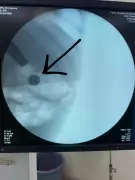

Doctors at Fortis Hospital in Noida successfully removed a lithium button battery from a 20-month-old girl's stomach, highlighting the life-threatening risks of such ingestions in children.